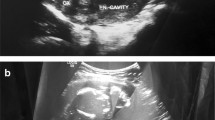

The patient was a 34-year-old Turkish woman, gravida 2 para 1 with a normal vaginal delivery 15 years previously. Although she had not used any contraceptive method afterwards, she had not become pregnant. She was transferred to our hospital from her local clinic at the gestation stage of 13 weeks because of pain in the lower abdomen and slight vaginal bleeding. She did not know when her last menstrual period had been, due to irregular periods. At admission, she presented with a history of abdominal distention together with steadily increasing abdominal and back pain, weakness, lack of appetite, and restlessness with minimal vaginal bleeding. She denied a history of pelvic inflammatory disease, sexually transmitted disease, surgical operations, or allergies. Blood pressure and pulse rate were normal. Laboratory parameters were normal, with a hemoglobin concentration of 10.0 g/dl and hematocrit of 29.1%. Transvaginal ultrasonographic scanning revealed an empty uterus with an endometrium 15 mm thick. A transabdominal ultrasound (Figure 1) examination demonstrated an amount of free peritoneal fluid and the nonviable fetus at 13 weeks without a sac; the placenta measured 58 × 65 × 67 mm. Abdominal-Pelvic MRI (Philips Intera 1.5T, Philips Medical Systems, Andover, MA) in coronal, axial, and sagittal planes was performed especially for localization of the placenta before she underwent surgery. A non-contrast SPAIR sagittal T2-weighted MRI strongly suggested placental invasion of the sigmoid colon (Figure 2).